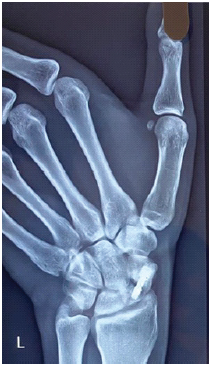

Proximal Hamate Autograft in Non-union Proximal Scaphoid Fractures, A Novel Technique – A Case Report

Ankit Kumar , Kishore Raichandani , Nirottam Singh

………………………………p.121-125